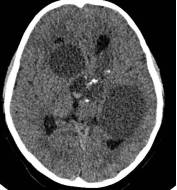

病例1:患儿男性,9岁。因反复出现意识丧失、视力降落半年收入院。入院后CT及 MRI显示颅内有形态不规则、“超大型”的颅咽管瘤,最大径约10厘米,见图1、图2。

图1.术前CT显示典型的囊性颅咽管瘤